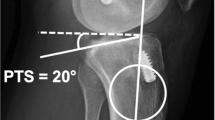

Posterior tibial slope measurement

Preoperatively available lateral radiographs were used to measure the medial PTS. To avoid measurement inaccuracies related to malrotated radiographs, the posterior femoral condyle overlap was measured and lateral radiographs with > 6 mm overlap were excluded [15, 16]. The medial PTS was measured using a previously described technique [17, 18]. First, the proximal tibial shaft axis was determined as a line connecting the centers of two circles located 5 cm and 15 cm distal to the joint line, respectively, which touched the anterior and posterior cortex of the tibia. Next, a tangential line was drawn to the medial tibial plateau. Finally, the angle between the proximal tibial shaft axis and the line tangential to the medial tibial plateau was subtracted from 90° to obtain the medial PTS (Fig. 1). Posterior tibial slope measurements were performed by observer one (PWW) using Philips iSite PACS (Koninklijke Philips N.V., Amsterdam, The Netherlands), which allows a measurement accuracy of 0.1 mm and 0.1°, respectively. To ensure intra- and interrater reliability of measurements, intraclass correlation coefficients (ICC) were calculated. For this, ten lateral knee radiographs were randomly selected and the medial PTS was measured three times at 2-week intervals by observer one (PWW) and once each by observer two (NNW) and three (JDH). Excellent intrarater (ICC, 0.99 95% CI [0.98, 0.99]) and good-to-excellent interrater (ICC, 0.92 95% CI [0.76, 0.98]) reliability of measurements was found.

Posterior tibial slope (PTS) measurement. Preoperative strict lateral radiograph of a right knee with isolated posterior cruciate ligament injury and a medial PTS of 6.7°. To obtain the medial PTS, the angle between the proximal tibial shaft axis (line 1) and a tangential line to the medial tibial plateau (line 2) was subtracted from 90°